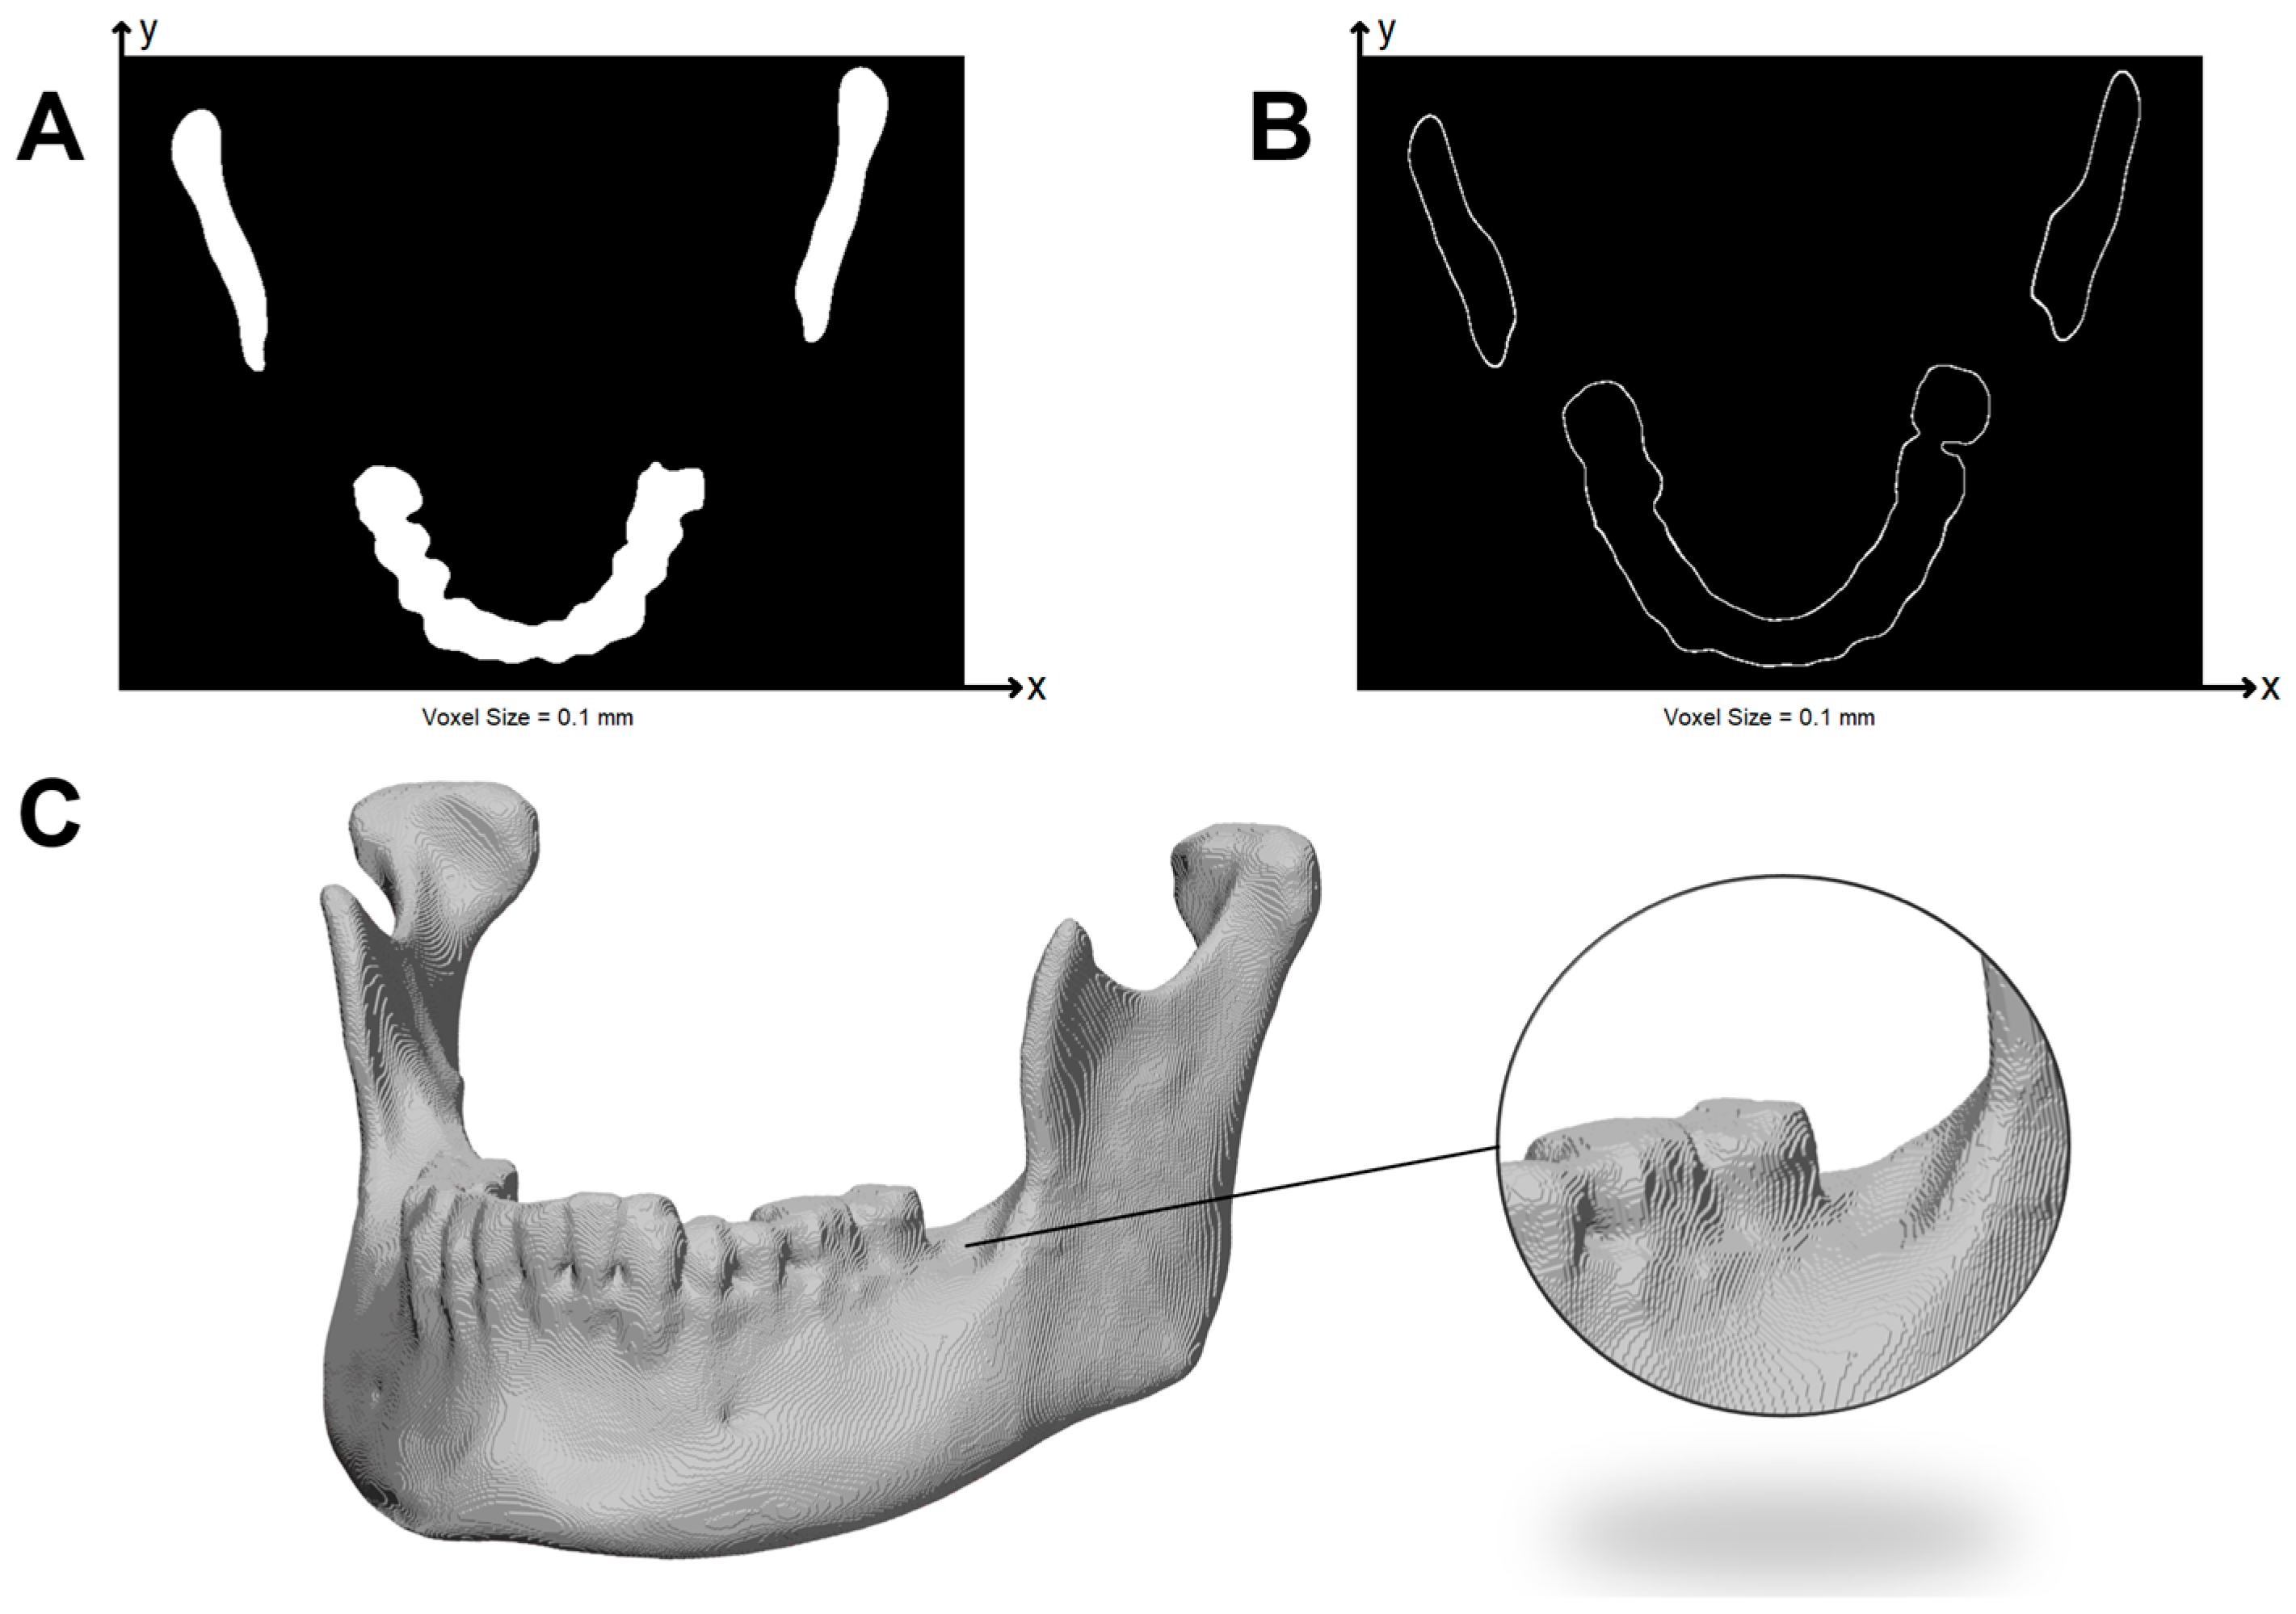

From this binary volume, a watertight surface was extracted using the marching cubes algorithm. Small voids were closed by morphological operations, and only the voxels corresponding to the outer shell of the object were retained. Infill points or inner perimeters were removed, as they do not influence surface or volumetric accuracy. This newly shell-only point cloud is called PC2. An example of the reconstructed volume and the axial view of the 3D binary label of the outer voxels are shown in Figure 2.

Figure 2. Voxel-based representation of the mandible after marching cubes reconstruction. (A) Axial view of the complete voxelized mandible. (B) Axial view showing only the voxels corresponding to the outer shell. (C) Three-dimensional rendering of the voxelized mandible.